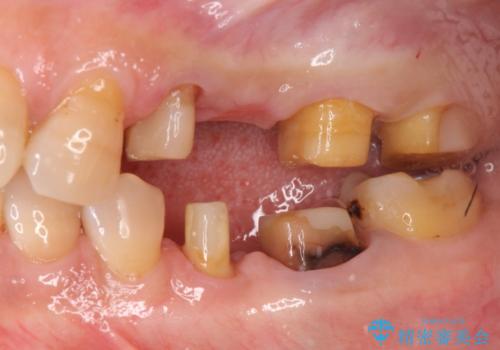

- 「老朽化し古くなった銀歯を白いものにやりかえたい。」と希望され来院されました。

銀歯の下には再発した虫歯やセメントの漏出が見られ、丁寧に除去したのちセラミックによるクラウン・ブリッジ補綴を行います。